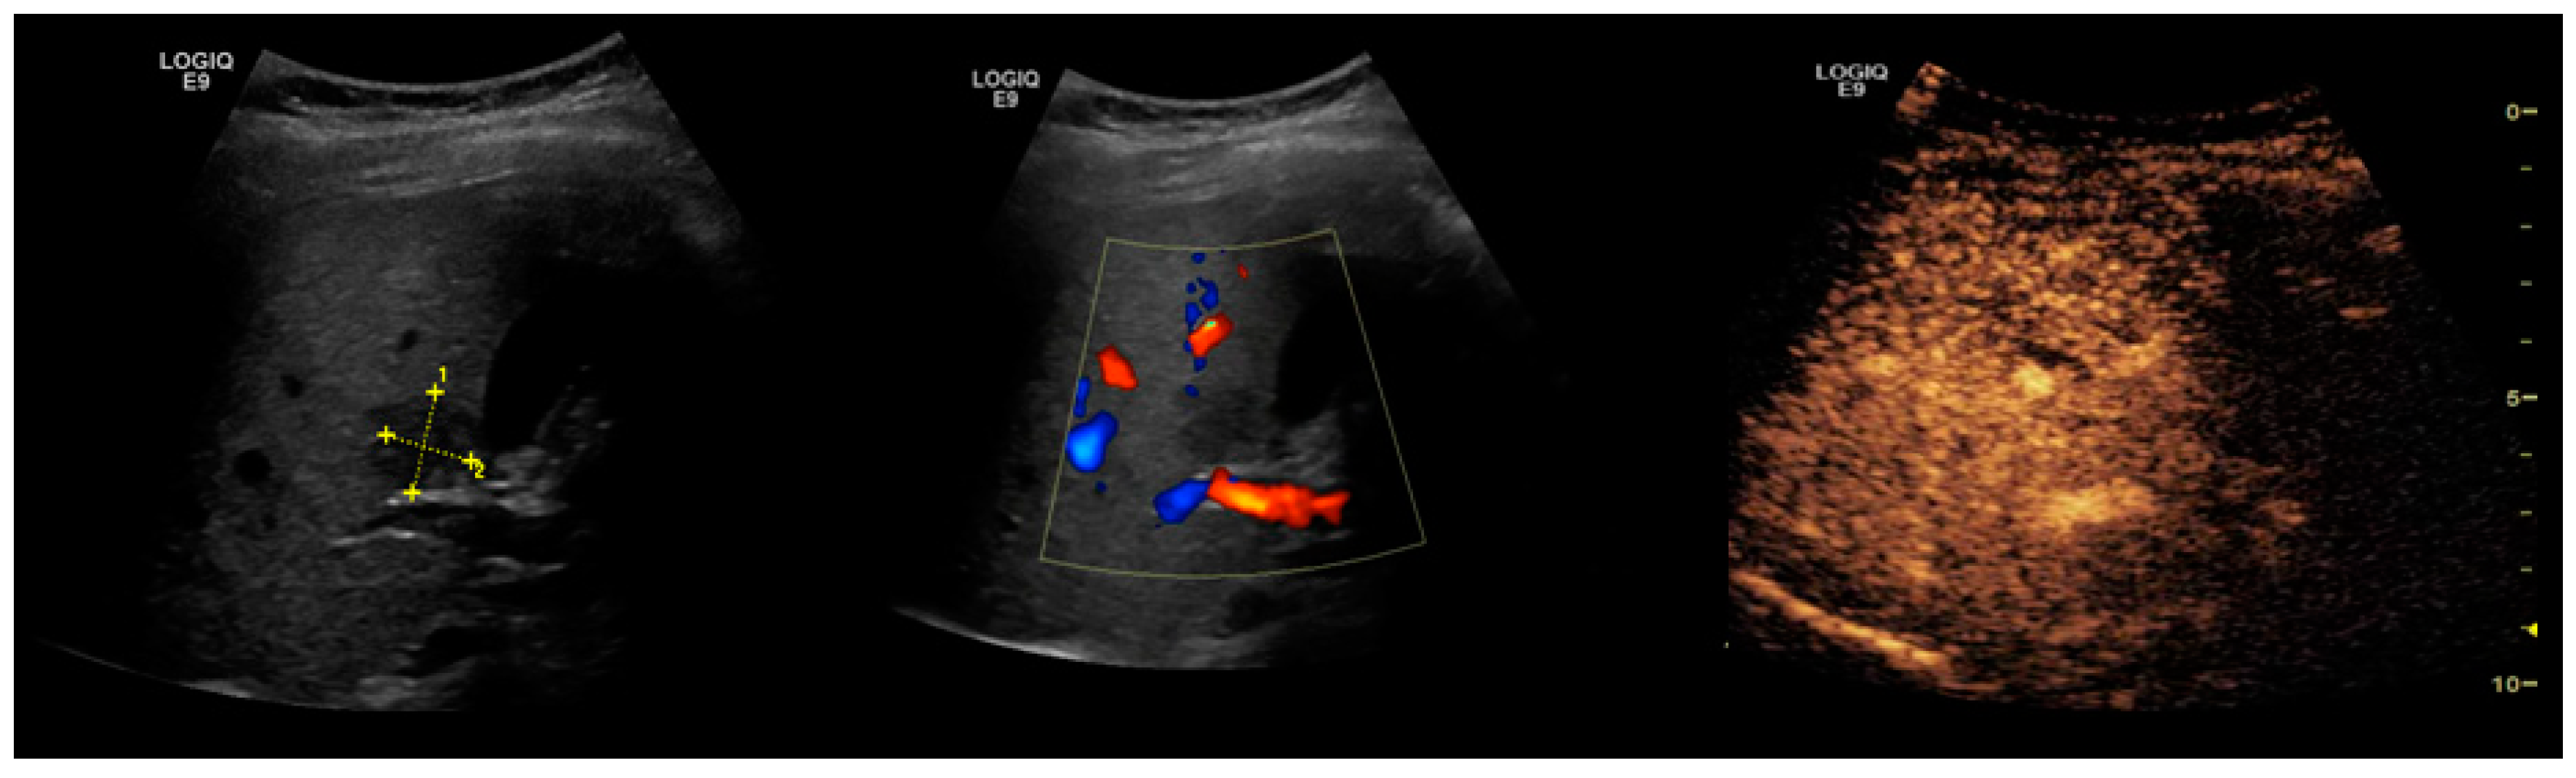

2.2. NAFLD-Related HCC: Could Conventional and Doppler US Differentiate between Focal Liver Lesions (FLLs)?

3. Contrast-Enhanced Ultrasonography (CEUS): An Add-on to the Diagnostic Power of Ultrasonography in NAFLD-Related HCC

- Tochio, H.; Kudo, M. Afferent and efferent vessels of premalignant and overt hepatocellular carcinoma: Observation by color Doppler imaging. Intervirology 2004, 47, 144–153. [Google Scholar] [CrossRef] [PubMed]

- Kudo, M.; Tochio, H.; Zhou, P. Differentiation of hepatic tumors by color Doppler imaging: Role of the maximum velocity and the pulsatility index of the intratumoral blood flow signal. Intervirology 2004, 47, 154–161. [Google Scholar] [CrossRef]

- Salvatore, V.; Bolondi, L. Clinical impact of ultrasound-related techniques on the diagnosis of focal liver lesions. Liver Cancer 2012, 1, 238–246. [Google Scholar] [CrossRef] [PubMed]

| Doppler US | Abnormal waveforms of the hepatic veins (normal triphasic pattern disappears) [81] Velocity of the portal flow (flow peak maximum velocity and mean flow velocity) and the portal vein pulsatility index (VPI) are significantly lower in patients with fatty liver when compared to the controls; it also corelates with the severity of the fatty liver [82] |